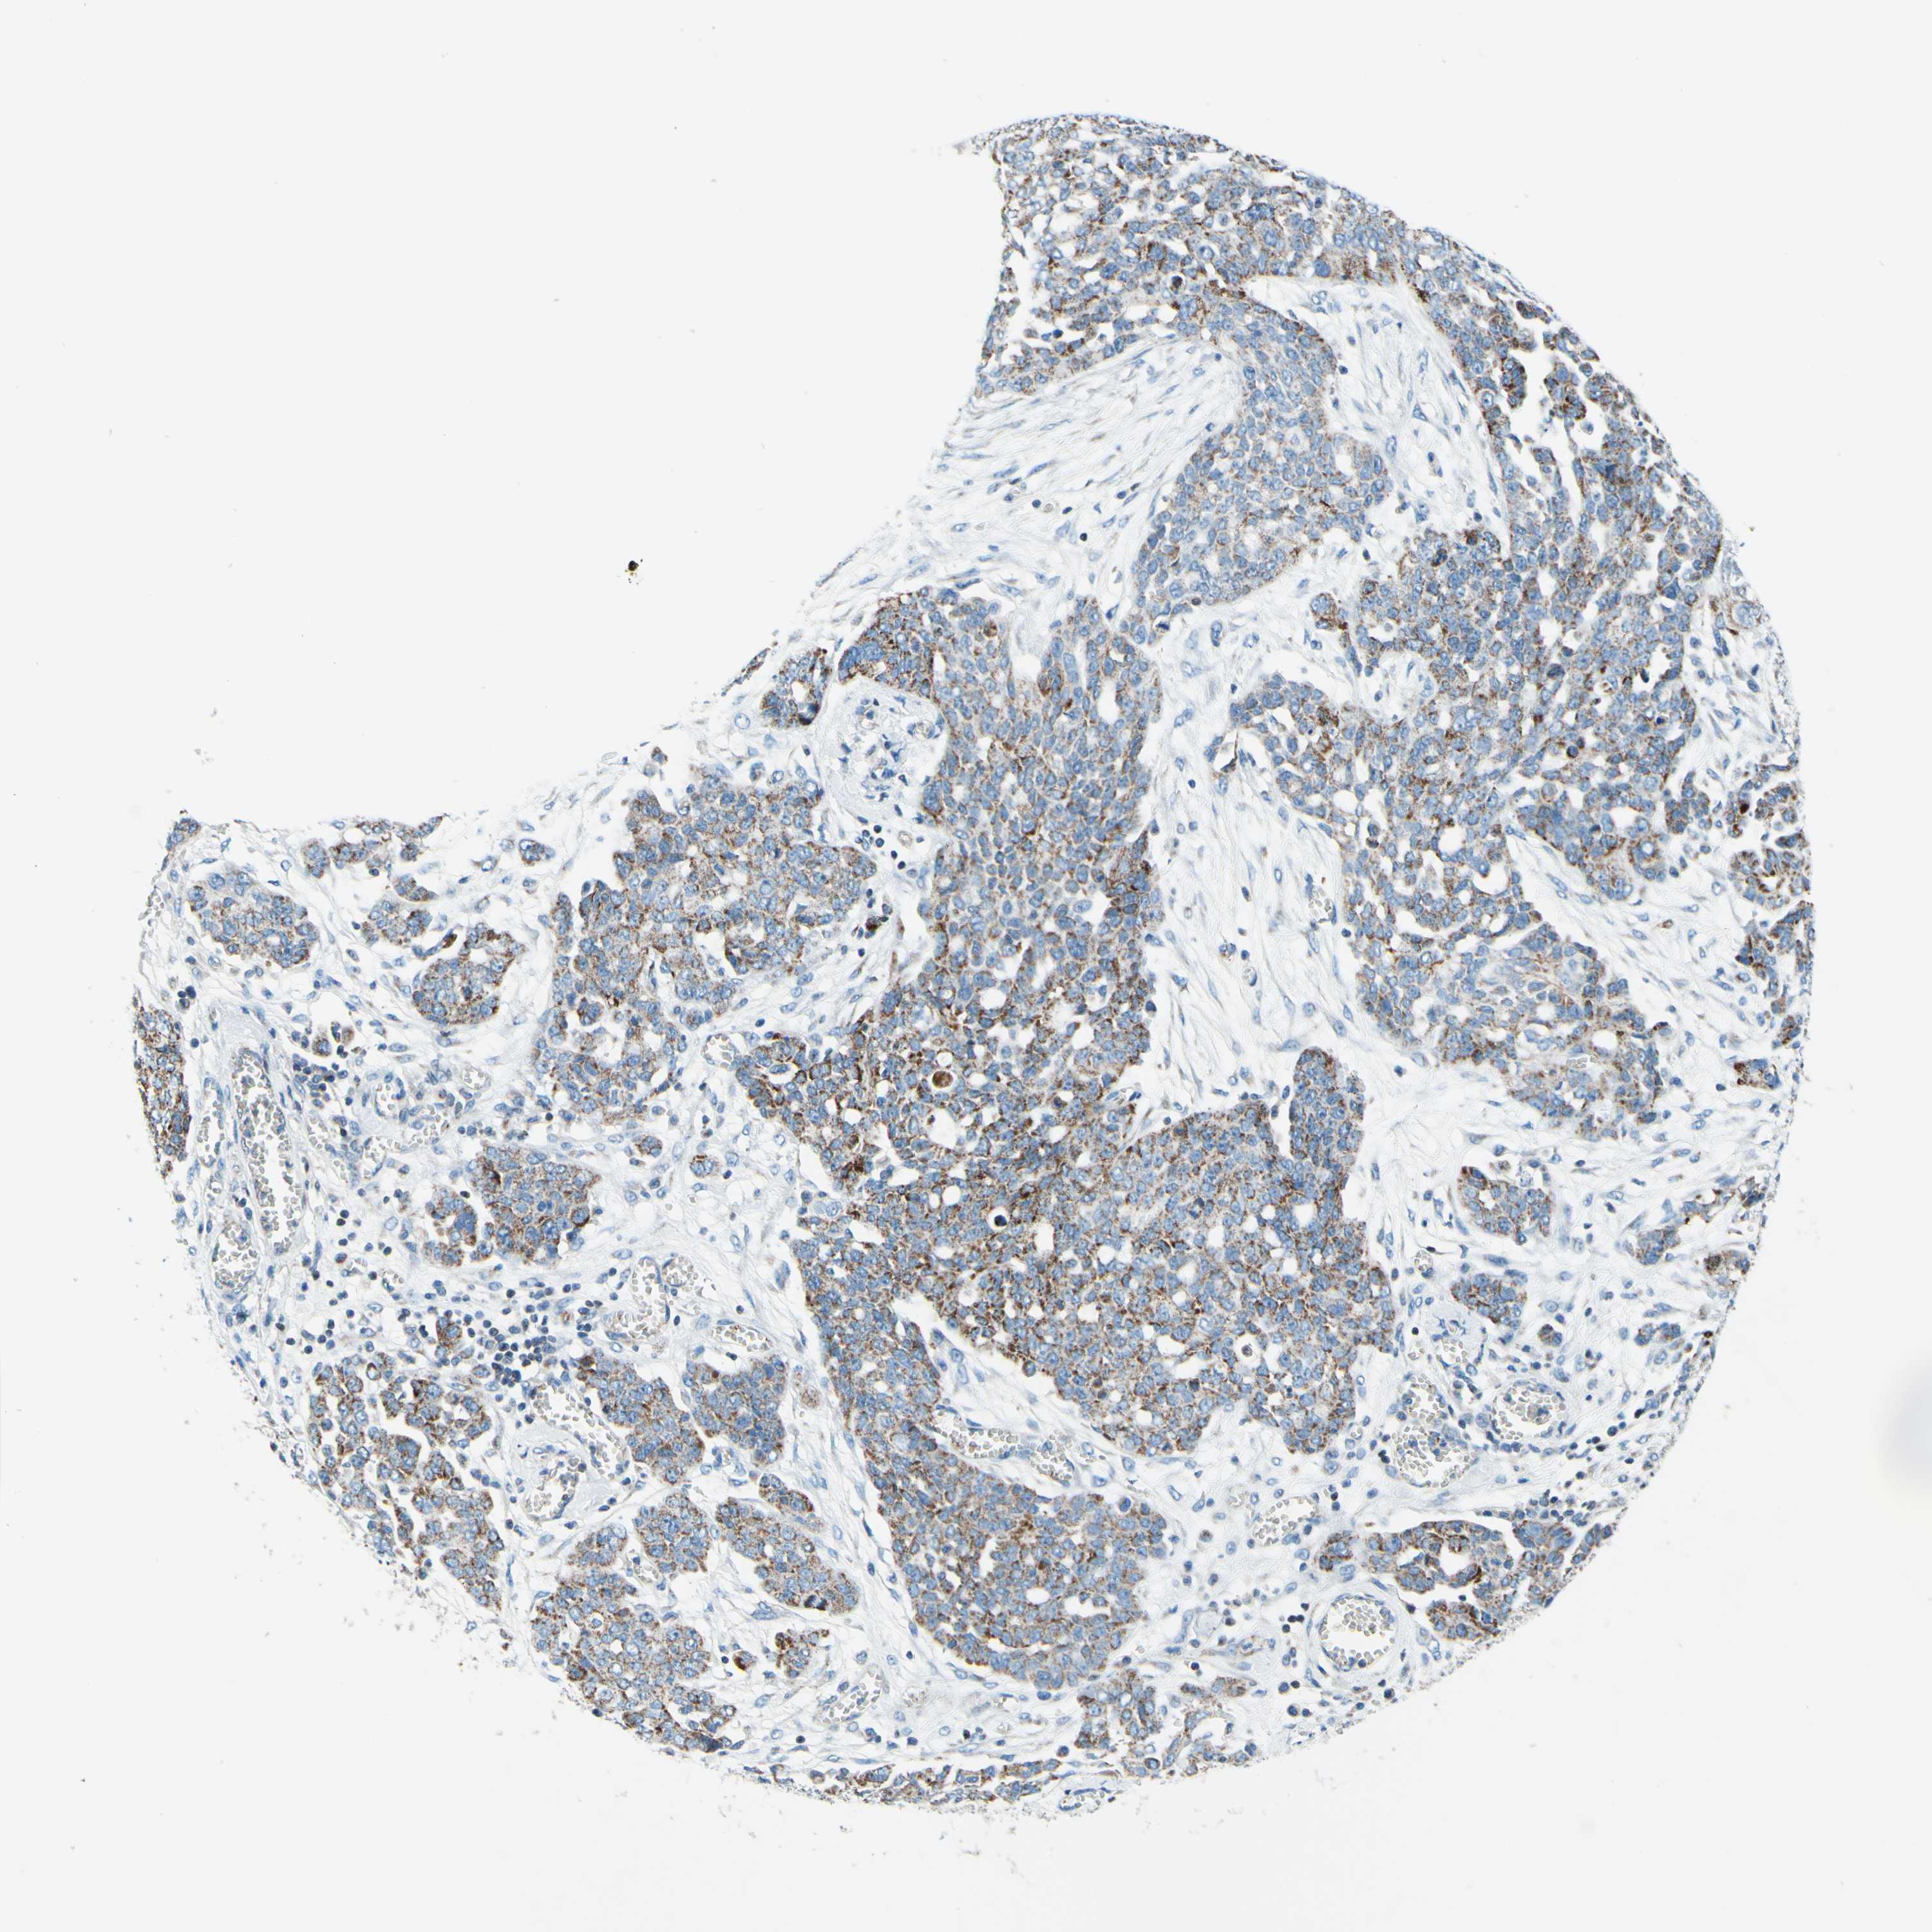

OVARIAN CANCER - Protein expressioni

A mouse-over function shows sample information and annotation data. Click on an image to view it in a full screen mode. Samples can be filtered based on level of antibody staining by selecting one or several of the following categories: high, medium, low and not detected. The assay and annotation is described here.

Note that samples used for immunohistochemistry by the Human Protein Atlas do not correspond to samples in the TCGA dataset.

Antibody stainingi

Antibody staining in the annotated cell types in the current human tissue is reported as not detected, low, medium, or high, based on conventional immunohistochemistry profiling in selected tissues. This score is based on the combination of the staining intensity and fraction of stained cells.

Each image is clickable and will lead to virtual microscopy that enables deeper exploration of all samples and also displays staining intensity scores, fraction scores and subcellular localization as well as patient and tissue information for each sample.

Antibody HPA048677

Antibody HPA056480

Staining

High

Medium

Low

Not detected

Intensity

Strong

Moderate

Weak

Negative

Quantity

>75%

75%-25%

<25%

None

Location

Nuclear

Cytoplasmic/membranous

Cytoplasmic/membranous,nuclear

Cystadenocarcinoma, serous, NOS